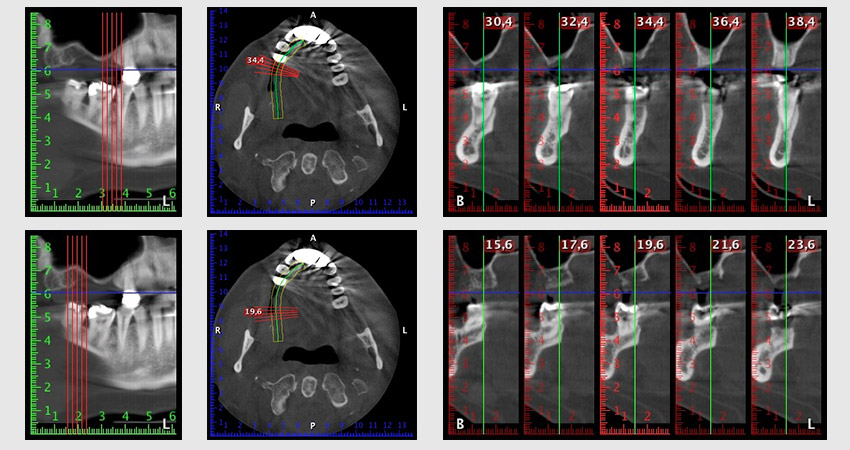

Etwa sechs Monate nach Extraktion der Zähne 16 und 14 wurde zur Planung und Risikominimierung eine digitale Volumentomografie (DVT, Planmeca) erstellt. Hierbei wurde deutlich, dass der Knochen sich nicht in der gewünschten Quantität regeneriert hat (Abb. 2 bis 7).